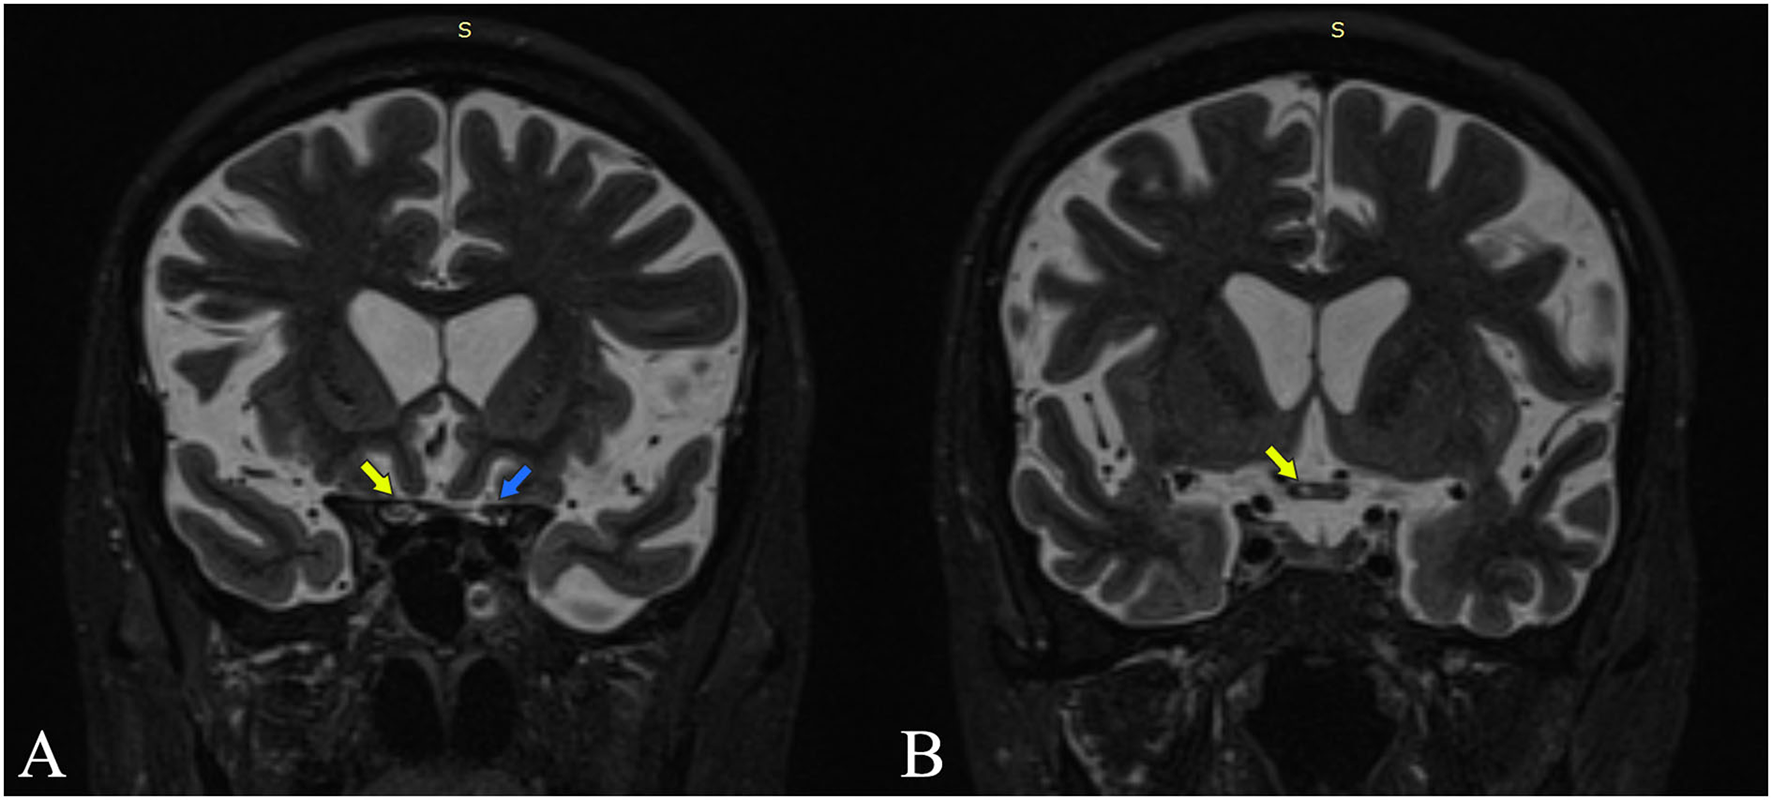

Figure 2

Coronal MRI STIR sections are at the intracranial optic nerves (A) and optic chiasm (B). Yellow arrows point out increased STIR signal intensity at the level of the right optic nerve and the right side of the chiasm. The blue arrow points out the left optic nerve with normal signal intensity.

The clinical picture of our patient, with posterior optical neuritis and cervical myelitis, was compatible with the anti-AQP4 phenotype. We believe the patient had suffered from optic neuritis with chiasmal involvement, with a clinical impact mainly on the right eye. This would explain the initially diminished visual acuity in both eyes and was supported by the MRI, which shows an extension of the inflammation in the optical chiasm (Figure 2).